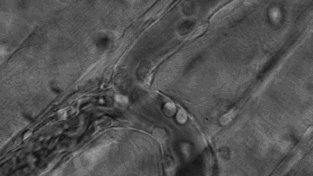

免疫细胞可穿过血管壁奔赴“战场”,向炎症和创伤组织进军、围剿。